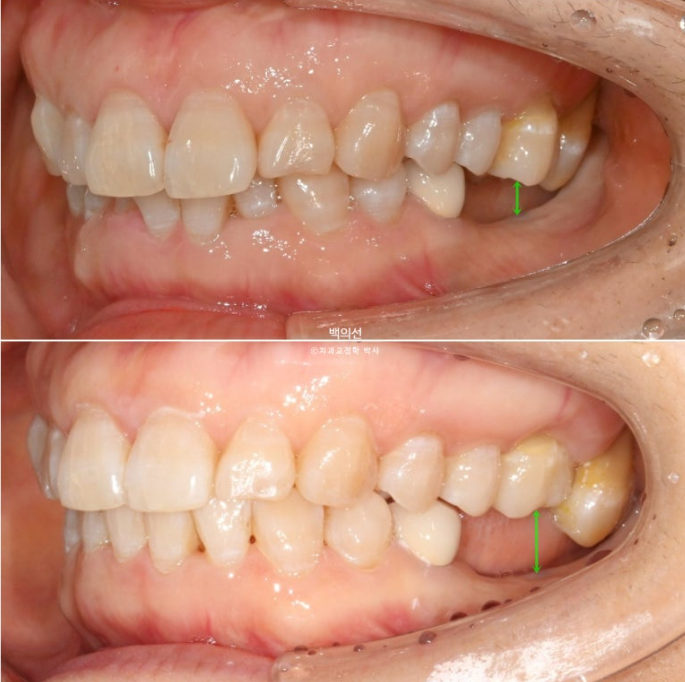

작년 9월, 앞니 돌출과 삐뚠치아 배열을 위해 오신 환자분입니다.

정면에서는 아래 앞니 일부가 윗니에 가려져 안 보일정도의 심한 과개교합을 보입니다.

좌측 아래는 어금니가 빠진 지 오래된 상태입니다.

임플란트가 필요한 부분을 장기간 방치하면 대합치가 조금씩 솟아 내려오게 됩니다.

파란화살표 임플란트를 해넣기 위해서는 교정으로 내려온 대합치를 합입 시켜 올려야 합니다.